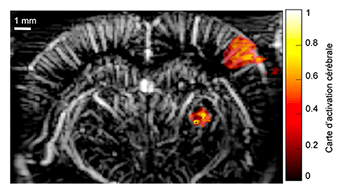

– Bioengineering and Innovation in Neurosciences (BIN)